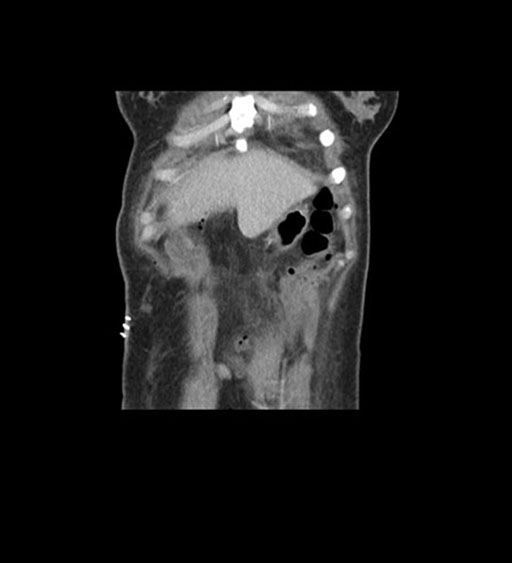

Coronal Arterial